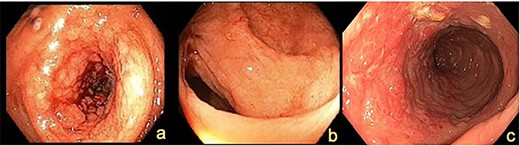

A 72-year-old female presented with abdominal pain and loss of weight. Computed tomography (CT) imaging demonstrated caecal and ascending colon thickening (Fig. 1a). Colonoscopy showed abnormal mucosa in the ascending colon that was unable to be traversed endoscopically (Fig. 2a) and slightly irregular mucosa at the hepatic flexure (Fig. 2b). The appearances were not typical of either a primary colon malignancy or a stricture secondary to inflammatory bowel disease (IBD). Biopsies were non-diagnostic, only showing mucosa with features of regeneration and repair. Given the patient was symptomatic, a laparoscopic right hemicolectomy was performed. Intraoperatively, a thickened firm ascending colon was seen suggesting possible submucosal involvement. Firm nodules were found in the terminal ileum mesentery and proximal transverse colon.

Colonoscopy demonstrating (a) ascending colon lesion, (b) hepatic flexure mucosal abnormality and (c) cobblestoned mucosa in the transverse colon.

CT imaging showed a thickening in the right colon (Fig. 1b). Colonoscopy revealed a stricturing lesion in the hepatic flexure, with abnormal cobblestone-type mucosa without ulcerations or erosions, which transitioned to normal mucosa near the splenic flexure (Fig. 2c). Endoscopic appearances could have represented Crohn’s disease given the cobblestoning but appeared atypical. Biopsies were unable to prove malignancy or IBD but demonstrated fibrosis with features of prolapse or healed ischaemic damage. There were no oestrogen-positive cells.

Colonic metastatic ILC often mimics other pathology in radiological and endoscopic investigations, namely primary colonic malignancy or IBD. On cross-sectional imaging, these lesions can appear as a diffuse mural thickening, with or without circumferential stenosis [7]. The endoscopic appearance is characterized by a multi-nodular cobblestone-like appearance of the mucosa, as shown in our report [8].